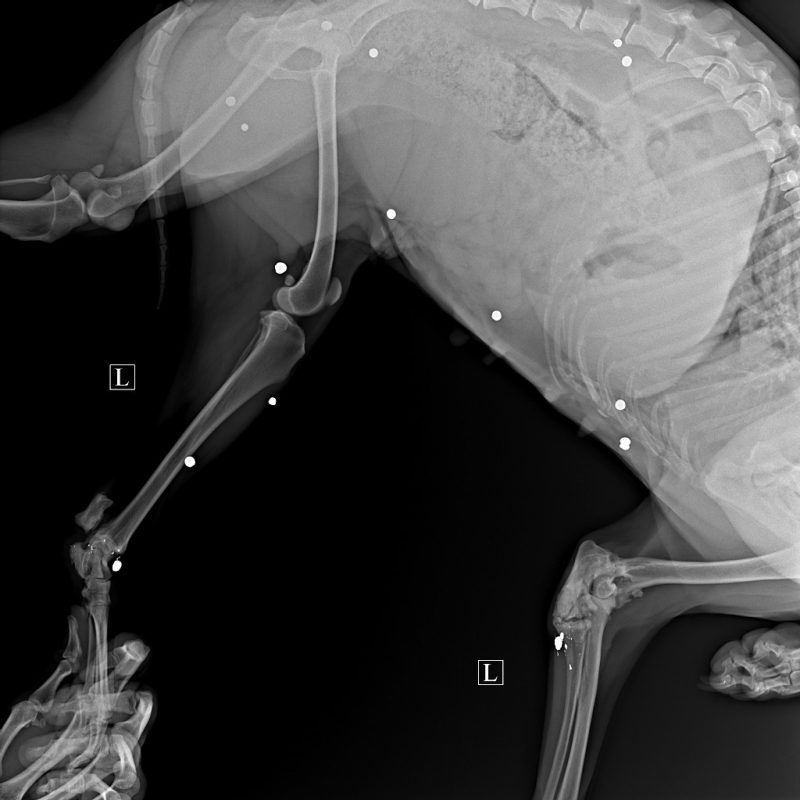

Каля мястэчка Сапоцкін знайшлі храмога сабаку. У целе жывёлы праз рэнтген выявілі больш за 20 куль. Адну з іх выцягнулі падчас аперацыі. Валанцёры шукаюць, хто страляў у сабаку.

Інцыдэнт адбыўся восенню 2021 года, магчыма раней. У сабакі пашкоджанні, зробленыя з выкарыстаннем агнястрэльнай альбо пнеўматычнай зброі, дапускаюць валанторы.